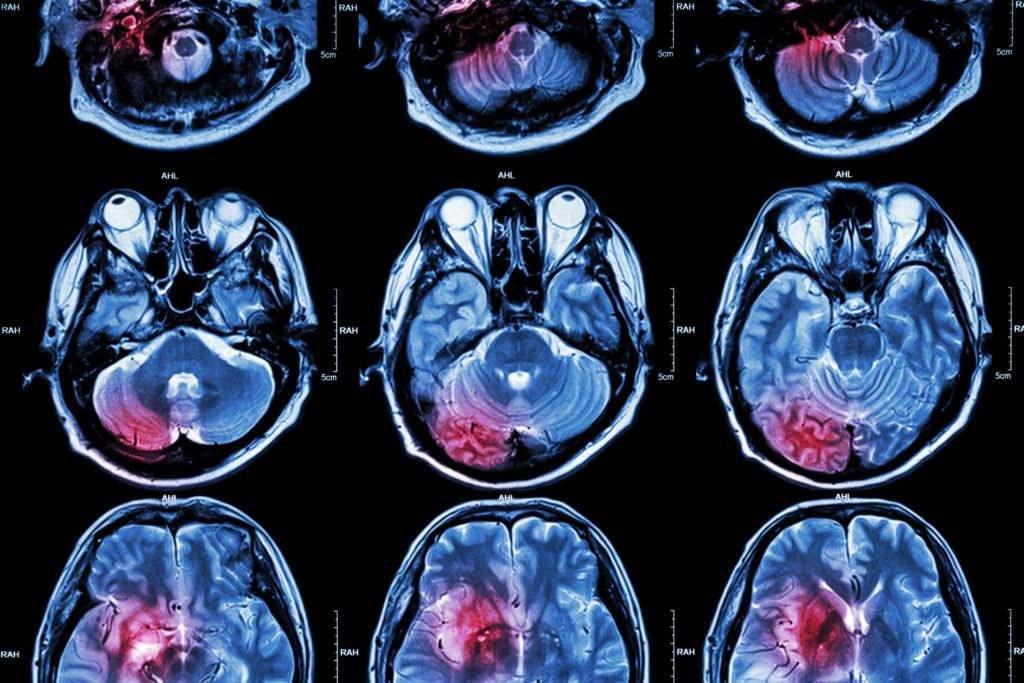

Henüz 14 yaşında olduğu için baş ağrılarının ergenliğin bir modülü olduğunu sanan Jade Jackson, “Teşhisim konulmadan evvel hayat hoştu. Birinci belirtileri gösterdiğimde 14 yaşındaydım ve baş ağrılarının hormonal olduğunu düşünüyorduk. Bir gün okuldan konuta gelip kendimi kanepeye attığımda daha önemli olduğunu fark ettim. Başımda anında dayanılmaz bir ağrı hissettim ve gidip kustum. O vakit bir şeylerin döndüğünü anladık. Oradan çabucak MRI çektirmeye gittik” halinde konuştu.